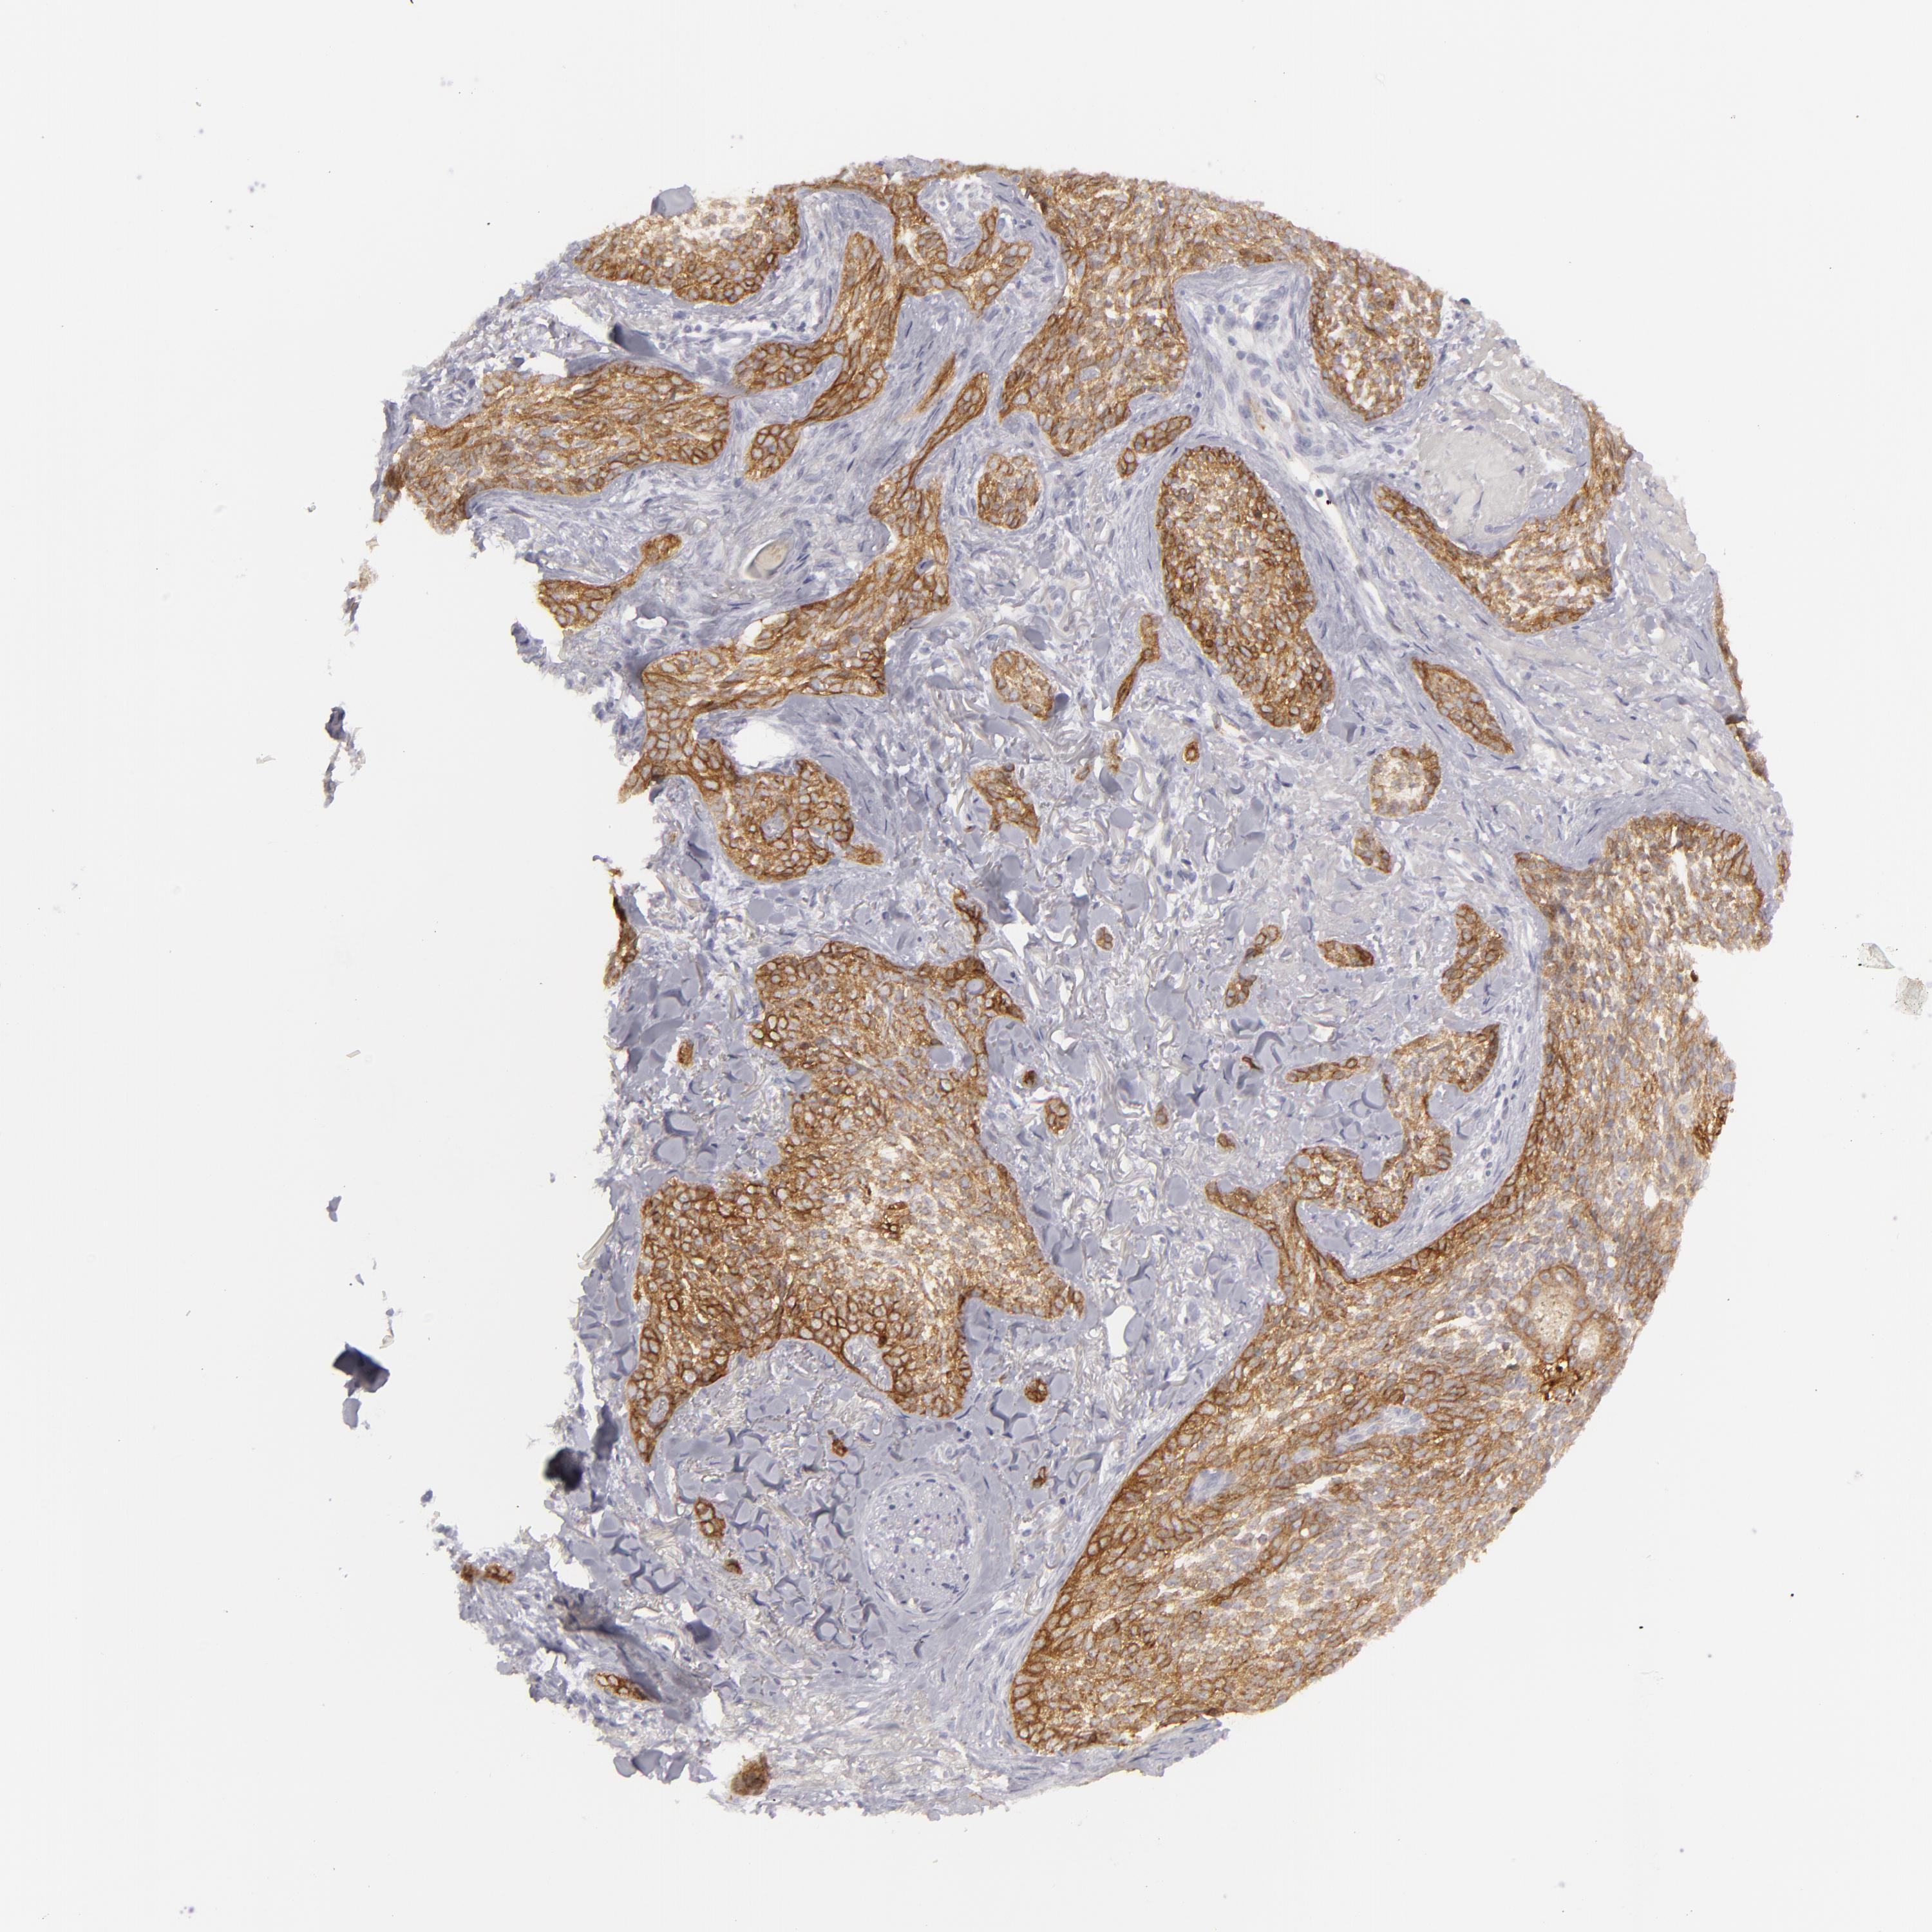

SKIN CANCER - Protein expressioni

A mouse-over function shows sample information and annotation data. Click on an image to view it in a full screen mode. Samples can be filtered based on level of antibody staining by selecting one or several of the following categories: high, medium, low and not detected. The assay and annotation is described here.

Antibody stainingi

Antibody staining in the annotated cell types in the current human tissue is reported as not detected, low, medium, or high, based on conventional immunohistochemistry profiling in selected tissues. This score is based on the combination of the staining intensity and fraction of stained cells.

Each image is clickable and will lead to virtual microscopy that enables deeper exploration of all samples and also displays staining intensity scores, fraction scores and subcellular localization as well as patient and tissue information for each sample.

Antibody HPA032047

Antibody CAB002139

Staining

High

Basal cell carcinoma

Squamous cell carcinoma, NOS

Squamous cell carcinoma, metastatic, NOS